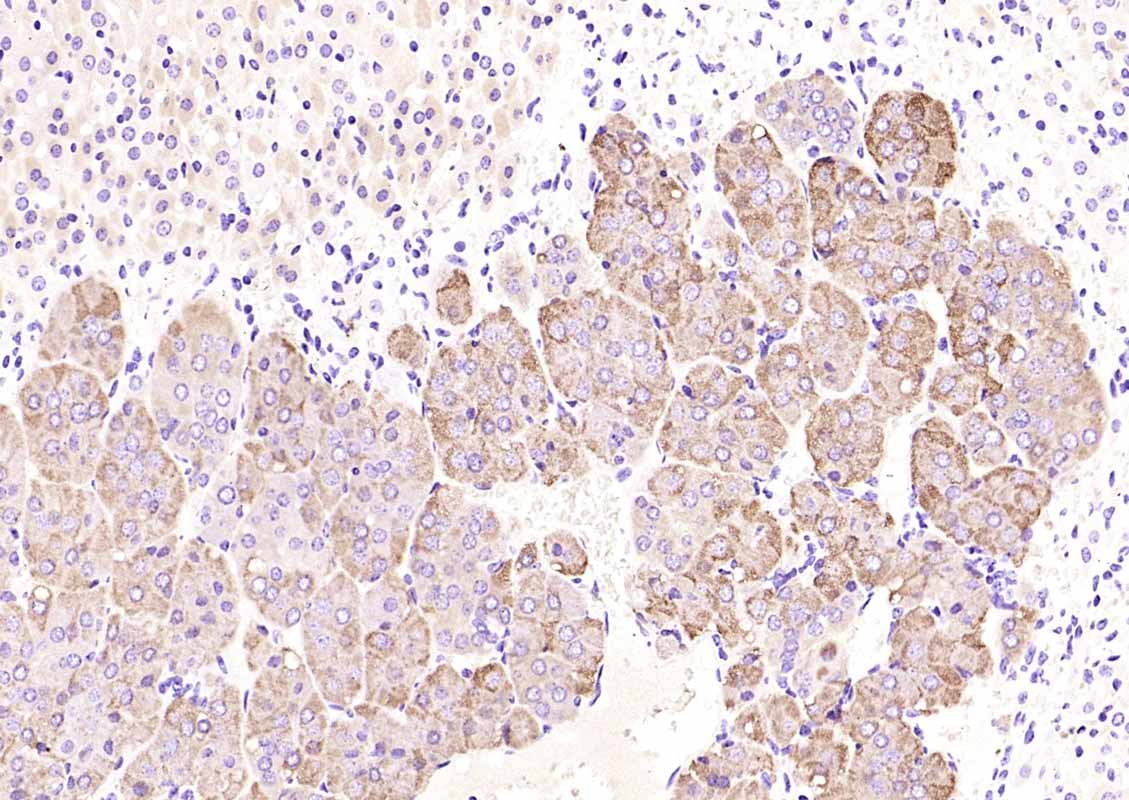

Paraformaldehyde-fixed, paraffin embedded (Human pancreas); Antigen retrieval by boiling in sodium citrate buffer (pH6.0) for 15min; Block endogenous peroxidase by 3% hydrogen peroxide for 20 minutes; Blocking buffer (normal goat serum) at 37°C for 30min; Incubation with (Chromogranin B) Polyclonal Antibody, Unconjugated (bs-0543R) at 1:200 overnight at 4°C, followed by operating according to SP Kit(Rabbit) (sp-0023) instructionsand DAB staining.